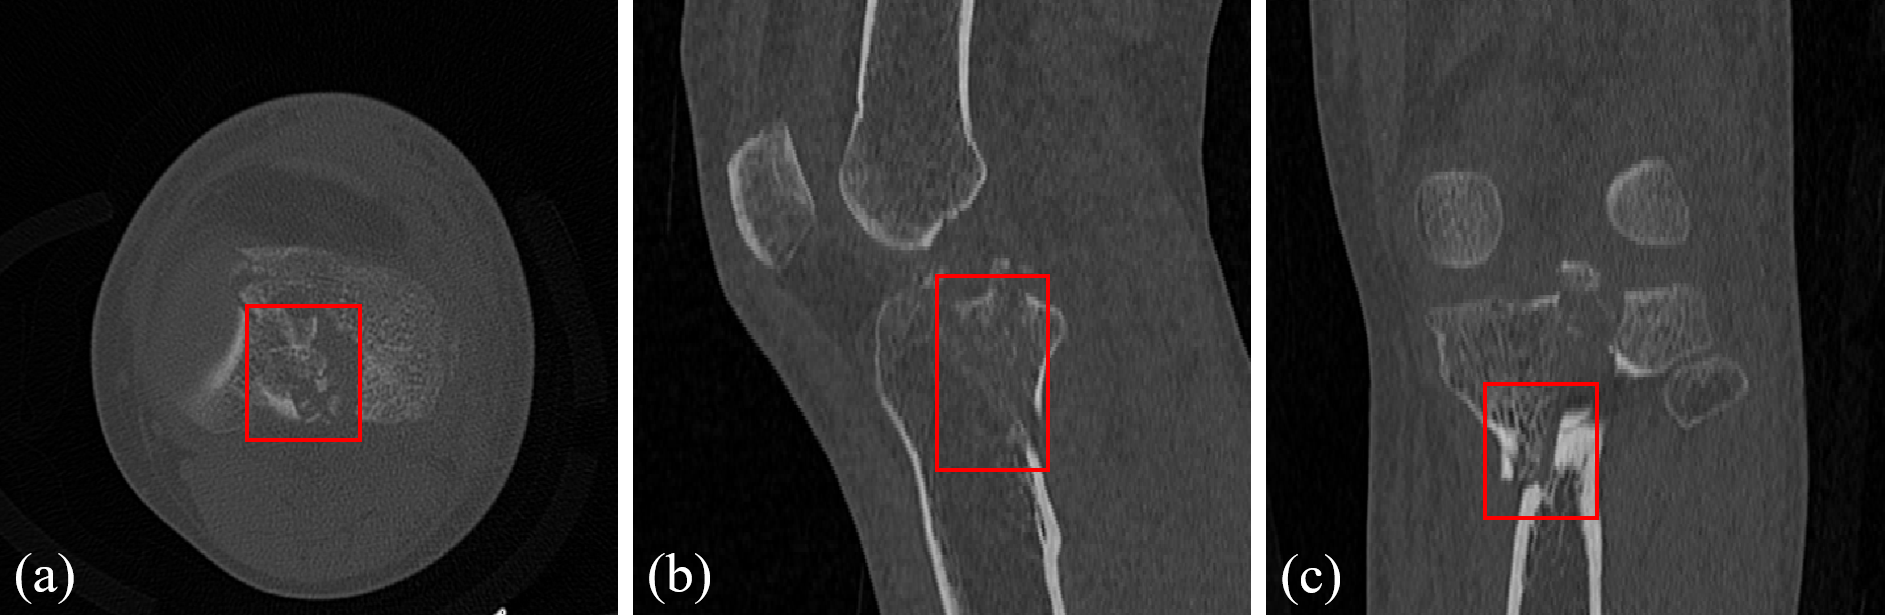

Refer to caption

Figure 1: Illustration of tibial plateau fractures (TPF) in computed tomography (CT) slices from three different views: (a) axial view, (b) sagittal view, and (c) coronal view. The fractures exhibit considerable variability in location and morphology, with some fragments being particularly difficult to distinguish, presenting huge challenges for the accurate segmentation.

Semi-supervised learning, which utilizes a small set of labeled images in combination with a large pool of unlabeled images, has been successfully applied to various bone segmentation tasks [2, 3, 4, 5, 6, 7, 8, 9]. However, these semi-supervised learning methods still face limitations in TPF segmentation tasks. Firstly, existing semi-supervised learning methods for bone segmentation often rely on consistency regularization or self-training approaches [10, 11, 12, 13, 14, 15]. These methods typically use predictions generated by a teacher model on unlabeled data to supervise the training of a student model. However, as shown in Fig. 1, the diverse types and complex fragment morphologies of TPF pose huge challenges. Models trained on a small set of finely annotated data struggle to generate high-quality predictions for these highly variable fracture regions, ultimately affecting the overall training performance. Secondly, models trained using semi-supervised learning methods often exhibit satisfactory performance only on specific datasets, making it difficult to generalize or transfer their effectiveness to other datasets.